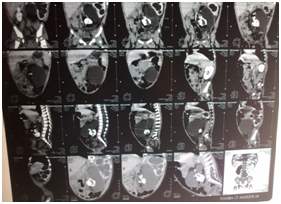

Clinical examination of the patient revealed soft abdominal mass occupying the left hemi-abdomen. Ultrasonography exam had shown a left hydronephrosis associated with polycystic mass measuring 10x15cm containing multiple calcifications. CT scan exam revealed a left hydronephrosis with a thin renal cortex associated with a well-capsulated and heterogeneous mass containing multiple calcifications, measuring 82x66x59mm, localized in the retro-peritoneum space and adherent to the lumbar vertebral column and the left iliac crest, pushing away the aorta and the inferior vena cava to the right side of the abdomen and compressing the left ureter (Figure 1). We suspected with teratoma. Contrast multislice computed tomography of the abdomen was done and it shew a bony mass lying on the left iliac crest and is adherent to the fifth lumbar vertebra and it receives blood perfusion through small vessel arising from the aorta (Figure 2). On surgical laparotomy and exploration using transverse left infra-umbilical incision, we found a large retro-peritoneal cystic mass adherent to the 5th lumbar vertebra and the left iliac crest, pushing the aorta and the inferior vena cava to the right side. There was no adherence with the left kidney but the ureter was compressed causing hydronephrosis.

Figure 1 CT scan shows well-limited cystic mass located in the left lower retroperitoneum containing multiple calcifications provoking a left major hydronephrosis.

Figure 2 Contrast multislice CT scan shows a bony mass attached to the fifth lumbar vertebra( yellow arrow).